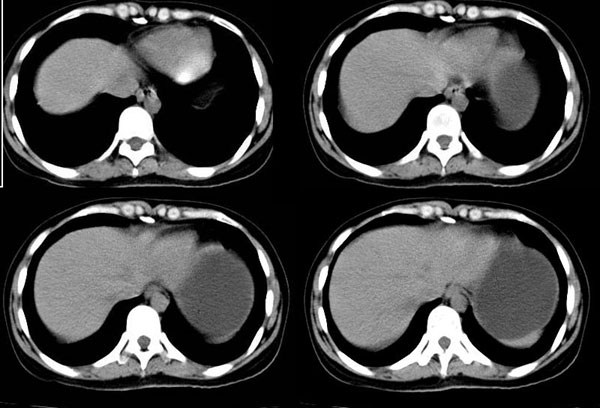

以下是引用guzhongliangddd在2006-11-9 17:55:00的发言:[br]请重点讨论图中箭头所示{脾门部,我首先考虑的是1:血管结构2:胰尾组织??)[br][br][本贴已被 guzhongliangddd 于 2006-11-9 18:01:50 修改过]

以下是引用西北偏北在2006-11-9 20:15:00的发言:[br]箭头所指结构边缘不光整,不支持副脾,考虑胰尾容积层面或血管,做个增强吧.